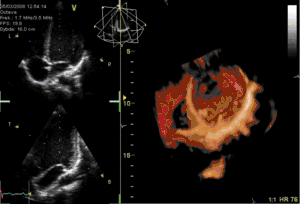

يتم تخطيط صدى القلب عبر المريء عن طريق مسبار يتم إدخاله عن طريق الفم إلى المريء، وذلك للحصول على "نافذة" أفضل موجات فوق صوتية|للموجات فوق الصوتية]] لرؤية الأقسام الخلفية من القلب، إذ أن هذه الجوانب تكون بعيدة عن الصدر، فتكون الصور التي يتم الحصول عليها من الصدر غير واضحة، بينما حينما يتم الفحص من المريء - الذي يُجاور القلب من الخلف مباشرة - أدق للأقسام الخلفية، كما يمكن إنتاج صور ثلاثية الأبعاد[5] لصمامات القلب.

يسمح التصوير عبر المريء بتحقيق تصوير بتمييز أعلى، وبخاصة للتفاصيل الدقيقة لحجرات القلب وصماماته، وذلك لأن المريء يقع مباشرة خلف القلب، بدون وجود الرئة كحاجز معيق بين مسبار الفحص وحجرات القلب، إذ أن الرئة بما تحتويه من هواء تعتبر معيقاً كبيراً لعمليات التصوير باستخدام الموجات فوق الصوتية. وتكون الدقة التصويرية أعلى من التصوير عبر الصدر[2] لأن المسبار يكاد يكون ملامساً للجدار الخلفي للقلب، ولايفصل بينهما إلا جدار المريء الدقيق نسبياً.